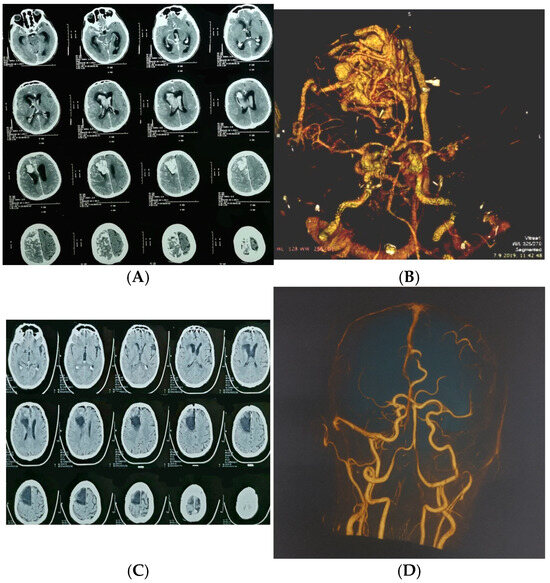

Occipital Pial AVM Rupture in a Young Adult: Dual Intranidal Aneurysms, Solitary Parasagittal SSS Drainage, and Hematoma-Corridor Microsurgical Cure

Background and Clinical Significance: Focal hemorrhagic severity associated with posterior convexity pial brain arteriovenous malformation (AVM) cases can be exacerbated by hemodynamic stress focusing on focal areas of architectural weakness and by superficial venous outflow being restricted by non-redundant superficial venous drainage. This [...] Read more.

Background and Clinical Significance: Focal hemorrhagic severity associated with posterior convexity pial brain arteriovenous malformation (AVM) cases can be exacerbated by hemodynamic stress focusing on focal areas of architectural weakness and by superficial venous outflow being restricted by non-redundant superficial venous drainage. This clinical case report exemplifies how bedside neurologic localization and angioarchitectural characteristics can inform the selection of microsurgical approaches for the treatment of ruptured AVMs that are directed at reducing hemorrhage recurrence risk through corridors based on rupture location. Case Presentation: An otherwise healthy young adult male (modified Rankin scale [mRS] pre-morbid = 0) initially presented with a thunderclap headache, emesis, photophobia, decreased level of consciousness (admitted Glasgow Coma Score [GCS] = 11; E3V3M5), and subsequent deficits including left-sided pyramidal weakness, visual field loss, and visuo-spatial neglect. A non-contrast computed tomogram (CT) confirmed an intraparenchymal hemorrhage (ICH) located within the right hemisphere’s posterior lobe. Angiographic evaluation of this AVM with catheter injection and three-dimensional reconstruction revealed a compact right occipital posterior convexity pial AVM (nidus 8 × 3 mm) supplied by distal cortical branches of the right middle cerebral artery (MCA); all blood draining from the nidus was directed to a single cortical vein which then drained into the superior sagittal sinus; there were two additional intranidal saccular aneurysms (approximately 3 × 2 mm and 3 × 3 mm). Because of the acute worsening secondary to ICH and because all venous drainage was superficial-only, a single-stage approach was selected given the urgency: decompressive evacuation of the hematoma via a corridor to the site of the AVM, followed by microsurgical removal of the AVM. The removal of the AVM was accomplished in a feeder-first, vein-last sequence, and en-passage arteries and parasagittal bridging veins were preserved throughout the procedure. Additionally, the two intranidal aneurysms identified as potential weak points during progressive devascularization of the AVM were specifically treated during the removal procedure. Following the successful removal of the AVM, the patient experienced a rapid recovery and returned to a nearly premorbid state of functioning, excepting a persistent small area of quadrantanopia. Conclusions: Rupture of posterior convexity AVMs may result in increased hemorrhagic severity due to localized architectural weaknesses in addition to the overall size of the AVM nidus. By correlating neurological findings, the topography of the hemorrhage, and angioarchitectural features early after rupture, emergency decisions regarding management can be better informed. The application of a hematoma-corridor, feeder-first/vein-last microsurgical approach for the treatment of such AVMs can achieve definitive curative results while minimizing damage to posterior cortical regions. Full article